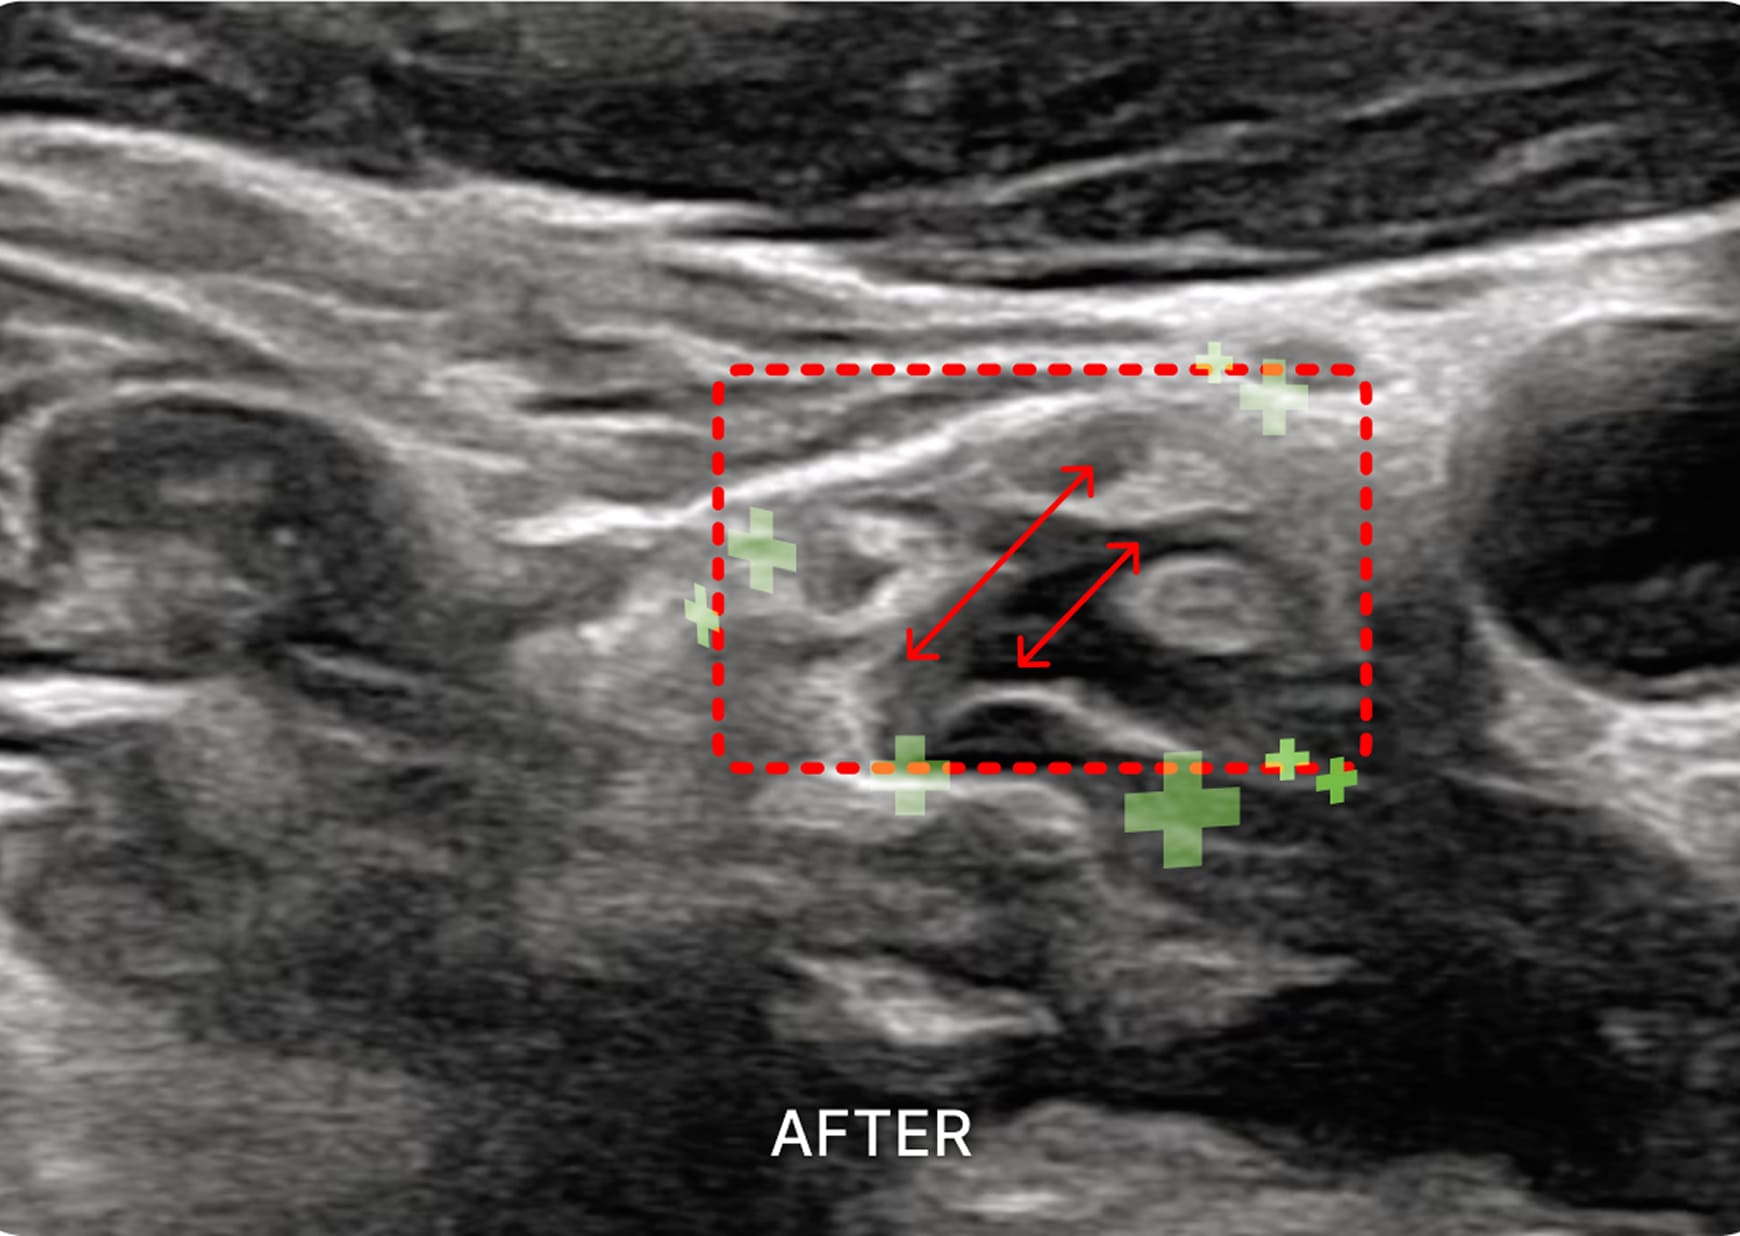

초음파 검사

1. 초음파 시술

초음파를 활용하여 근육과 신경 문제를

정확히 진단하고 치료하여 통증과 기능

이상을 개선하는 시술입니다.